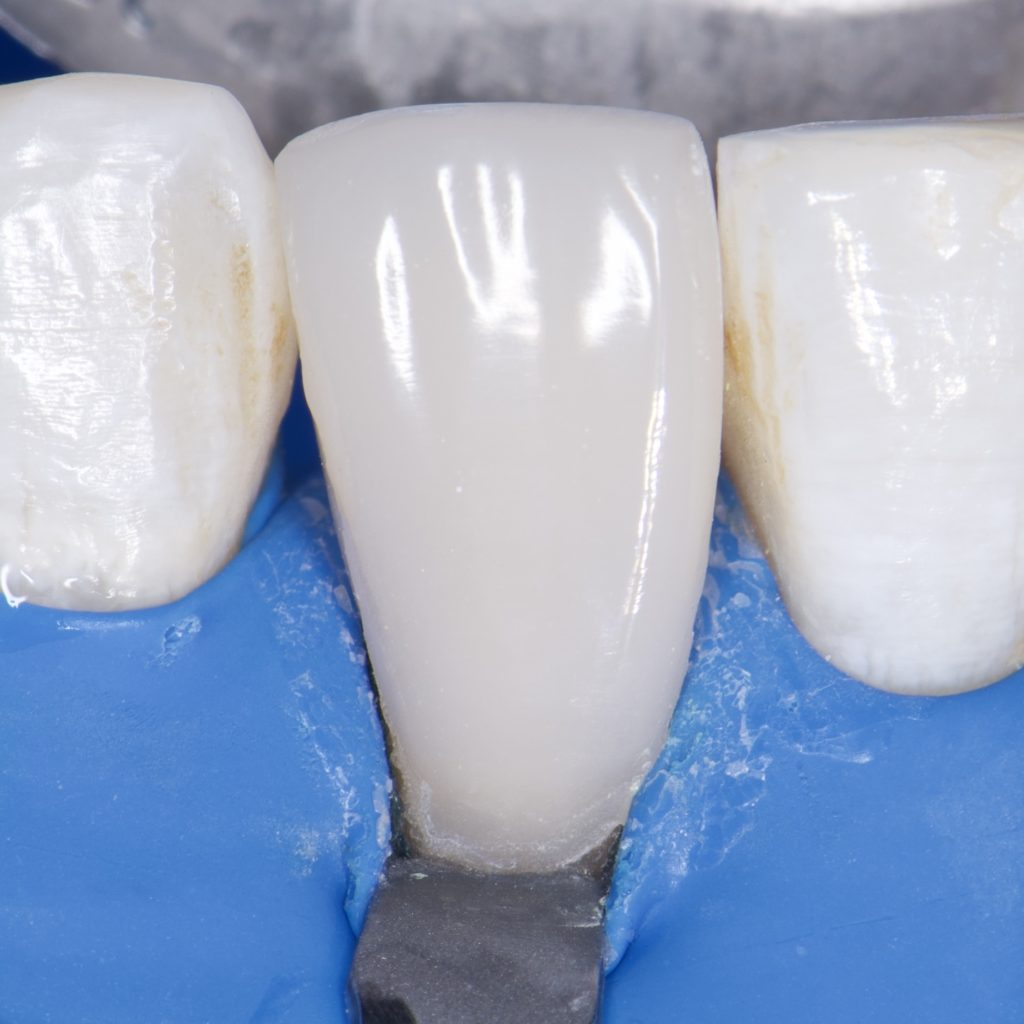

1 month Follow up